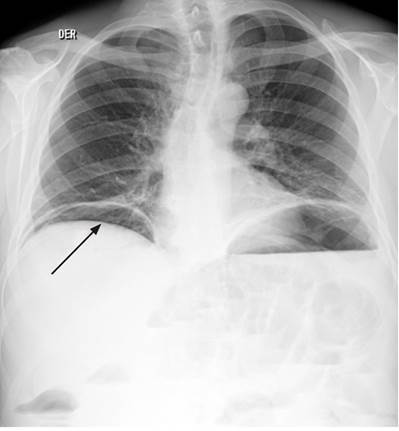

Se inició el manejo con líquidos intravenosos (y se logró normalidad hemodinámica) y cubrimiento antibiótico a base de ampicilina/sulbactam. Se solicitaron estudios paraclínicos que mostraron un hemograma con leucocitos: 15 530/μL, hemoglobina: 10,4 g/dL y plaquetas: 130 000/μL, además de proteína C-reactiva (PCR): 114 mg/dL, gases arteriales con pH: 7,31, presión parcial de dióxido de carbono (pCO2): 22,7 mm Hg, presión parcial de oxígeno (PO2): 70,3 mm Hg, bicarbonato (HCO3): 11,2 mmol/L y base exceso (BE): -12,7 mmol/L. Se realizaron radiografías de tórax de pie (Figura 1) y de abdomen simple (Figura 2).

Figura 2 Radiografía simple de abdomen. Se aprecian múltiples niveles hidroaéreos (flecha) que comprometen toda la cavidad abdominal, sobre todo en el mesogastrio y epigastrio, con presencia de aire en la ampolla rectal (obstrucción parcial o fenómeno de íleo).